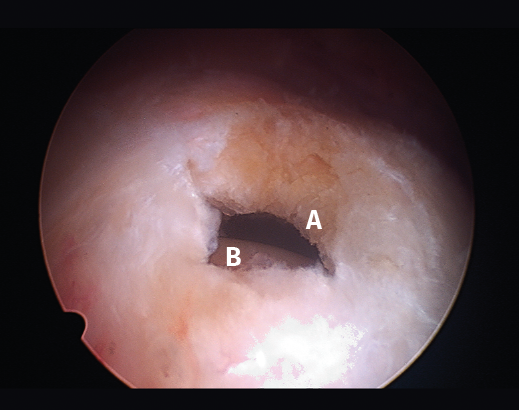

Figura 3. Rotura del manguito rotador en forma de L. A: tendón infraespinoso; B: tendón supraespinoso; C: glena; D: cabeza humeral.

Figura 5. Rotura de tipo C1. A: rotura pequeña de espesor completo del supraespinoso; B: cabeza humeral.

Sin embargo, las clasificaciones basadas en el tamaño de la rotura deben ser bidimensionales, ya que la visión unidimensional puede ser engañosa, al mostrar el tamaño de la rotura solo desde el plano anteroposterior(4). Por esta razón, proponemos el sistema de clasificación del manguito posterosuperior sugerida por Snyder, que aporta información no solo del tamaño, sino del número de tendones afectados y la presencia de tejido cicatricial(7). En las lesiones de tipo C1 la lesión atraviesa todo el espesor del tendón y en el eje transversal es pequeña y punzante (Figura 5). Las de tipo C2 son roturas de espesor completo pero la distancia entre los extremos de la rotura es menor de 2 cm con escasa retracción (Figura 6). En las de tipo C3 la rotura afecta en sentido transversal entre 3 y 4 cm con mayor retracción implicando 2 tendones (Figura 7). Y las de tipo C4 son la rotura masiva del manguito de los rotadores con una afectación de espesor completo de toda la anchura de 2 o más tendones asociando importante retracción (Figura 8).